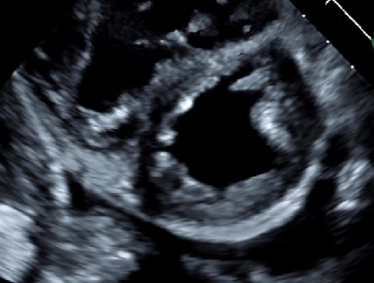

Καρδιακό υπερηχογράφημα. Διάταση δεξιάς κοιλίας, εύρημα ενδεικτικό πνευμονικής υπέρτασης (Ευγενική παραχώρηση Dr. V. Penopoulos)